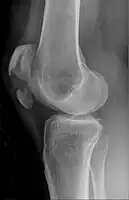

Some people have a normal two-part patella which can appear as a fracture. The fragment is usually seen in the top outer corner of the patella and can be distinguished from a fracture by being present in both knees.[6]